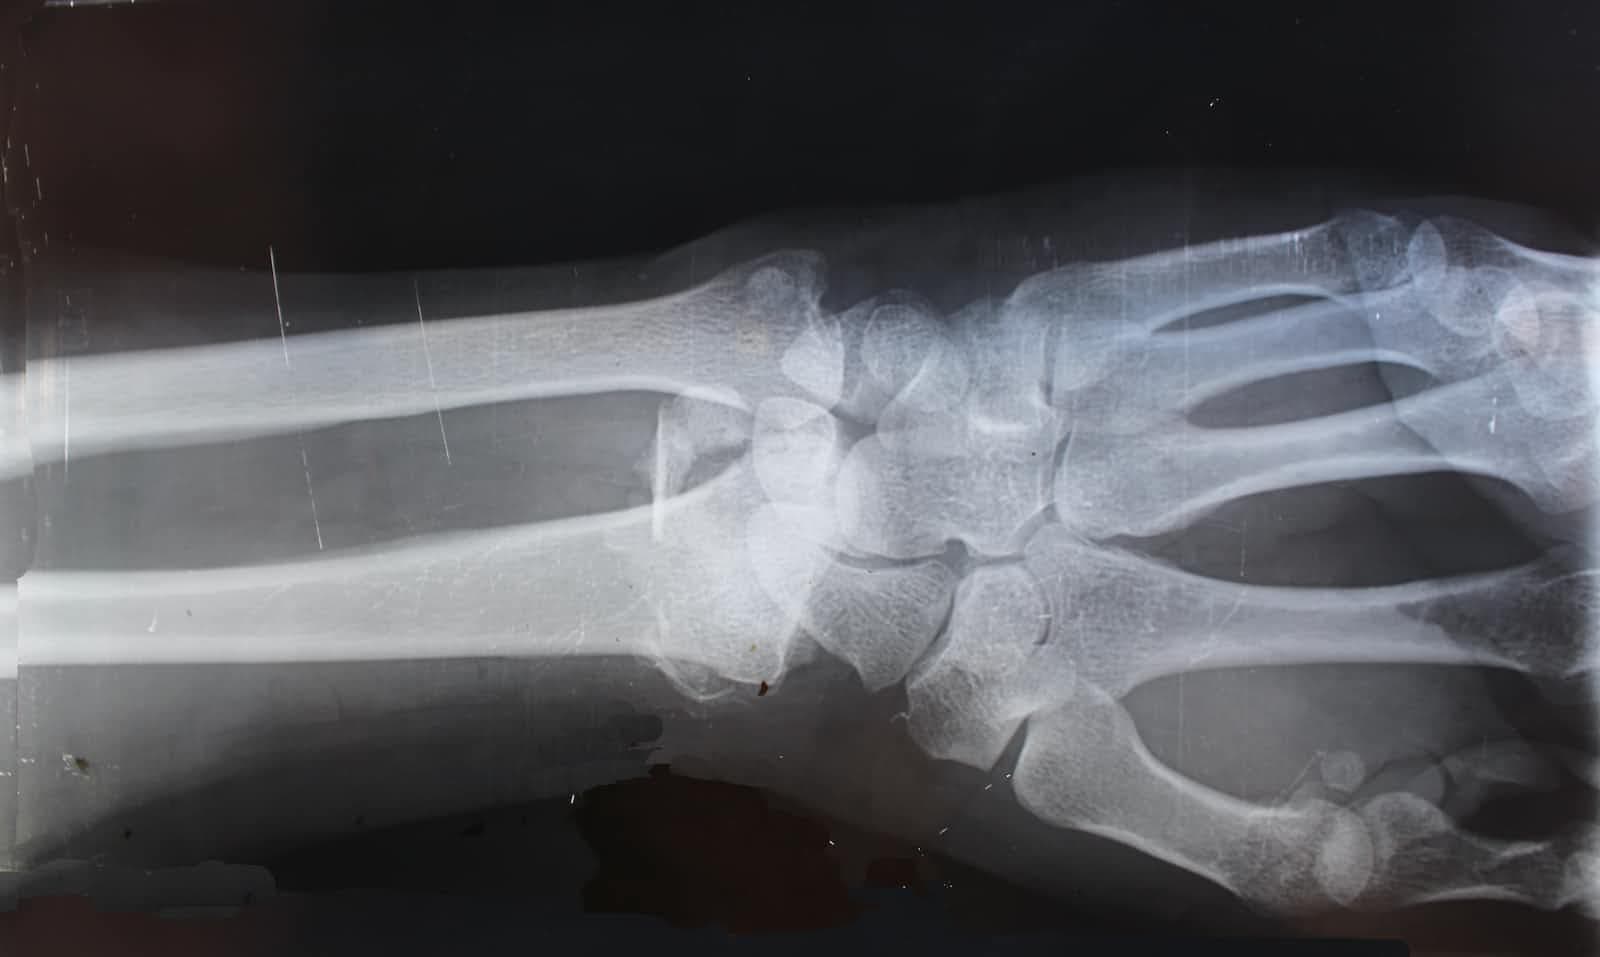

Not all pain is bad.A relative of mine had an accident. He got knocked down by a bus while he was waiting to cross the road and fractured his wrist. Being afraid of expensive treatment, he went to a traditional medicine man who helped set it back but left it misaligned....Jan 3, 2023·2 min read·149